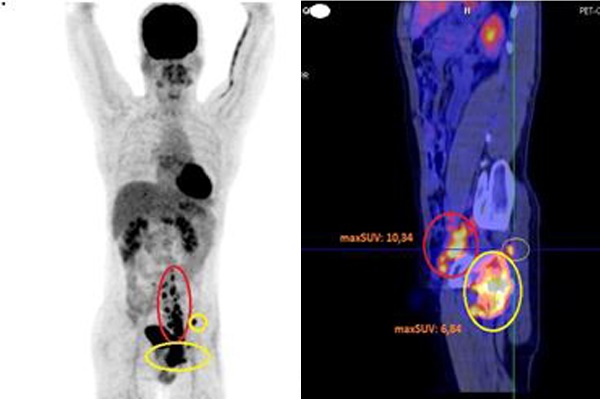

Kết quả điều trị sau 4 tháng

Kết quả chụp PET/CT lần 2 cho thấy, cả số lượng và kích thước hạch đều giảm, trong đó hạch dọc động mạch chủ bụng, bẹn trái đã giảm còn 1x2 cm, hạch vùng hố chậu trái còn 3,2x2,1x2 cm. Tuy nhiên xương chậu trái vẫn bị tổn thương nhiều, phá hủy xương và xâm lấn phần mềm xung quanh.

Ở các liệu trình điều trị tiếp theo, bệnh nhân đáp ứng tốt với hoá chất, các tổn thương đa ổ không còn nhìn thấy, khối u nhỏ dần.